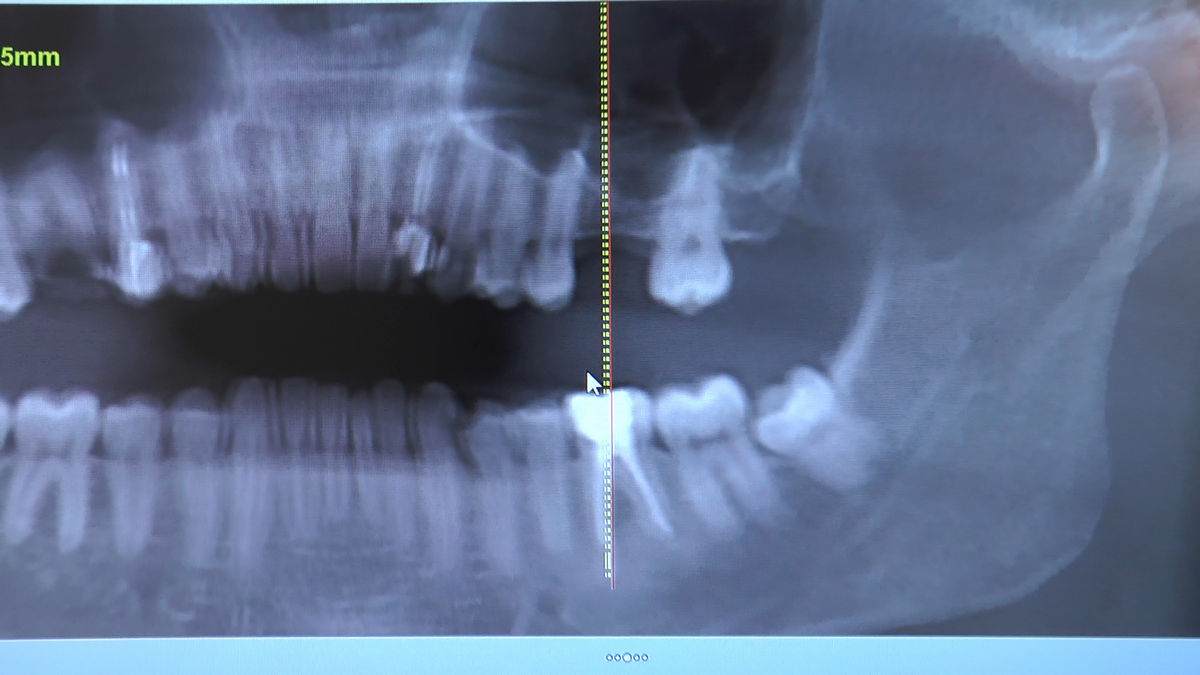

Practiculum Implantologii – Sezon VI, sesja 3, część 1